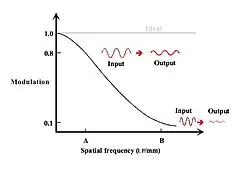

When the Fourier Transform of an LSF is calculated, then the imaging system’s response to sine waves of all spatial frequencies is obtained. This response is called the Modulation Transfer Function (MTF) - see Figure 6.9. It can be seen that the modulation falls off with increasing spatial frequency, as was seen with the Square Wave Response, but as a continuous curve representing all, and not just discrete, spatial frequencies.

The response of an ideal imaging system is also shown in the figure. Its constant value of 1.0 at all spatial frequencies implies that all details in the patient will be imaged perfectly, unlike our real intensifying screen whose modulation drops by 20% at spatial frequency, A, and by 90% at frequency, B, for example - whatever their absolute values might be.